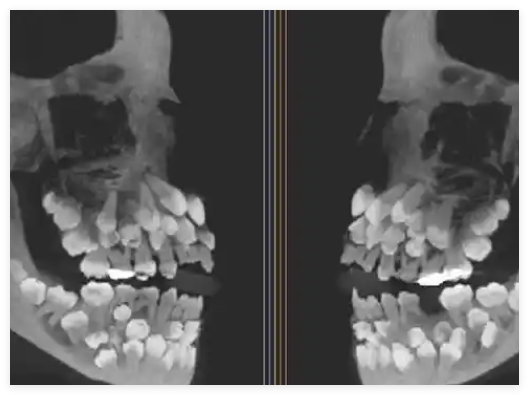

巴西米納斯吉拉斯州一名11歲女孩被發(fā)現(xiàn)口中竟有多達(dá)81顆牙齒,引發(fā)醫(yī)學(xué)界震動。該罕見病例由巴西聯(lián)邦大學(xué)Juiz de Fora的醫(yī)生團(tuán)隊(duì)記錄,并于近日發(fā)表在《美國正畸與頜面外科雜志》上。

女孩原本只是前往牙科檢查,打算拔除殘留的乳牙,X光檢查卻發(fā)現(xiàn)她不僅有18顆乳牙和32顆恒牙,還額外長出了31顆“超生牙”,屬極罕見的“多重超數(shù)牙”病例。

通常此類患者僅多出少量牙齒,而這名女孩卻未攜帶任何已知相關(guān)遺傳綜合征,令人困惑。

醫(yī)生通過CT掃描及染色體檢測,發(fā)現(xiàn)其第9號染色體存在一處罕見變異,但目前尚無法確認(rèn)該變異是否直接導(dǎo)致牙齒異常。

女孩目前需接受多學(xué)科聯(lián)合治療,制定精準(zhǔn)拔牙與整形計(jì)劃,以保護(hù)頜骨健康,恢復(fù)正常咀嚼功能與面部美觀。